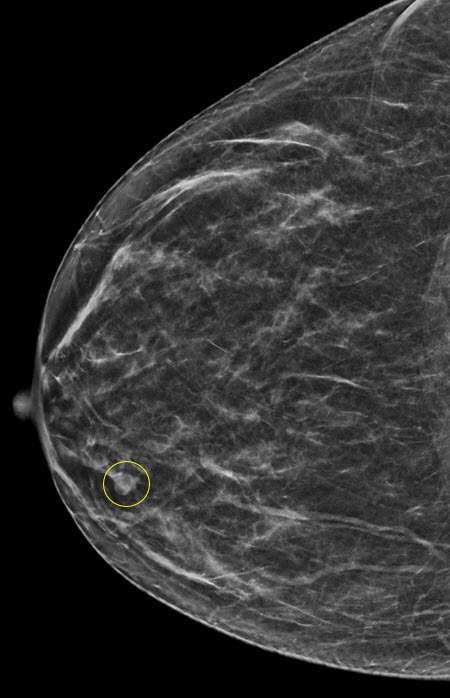

Case: Breast Ductal Anatomy and Function Figure 4

Figure 4: A craniocaudal mammogram showing a circumscribed mass in the right inner breast, which was biopsied and found to be a papilloma